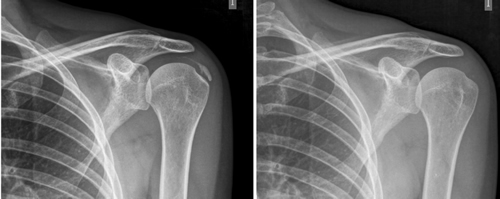

Resultados: Edad media: 54,6 años (n = 138); mujer (73,1 %; n = 101); proporción mujer/hombre 3: 1; tendón supraespinoso (94,6 %; n = 124); subescapular (5,4 %; n = 14); hombro izquierdo (55,1 %; n = 76), hombro derecho (44,9 %; n = 62); bilateral 1,4 % (n = 2); diestros 96,3 % (n = 133); antecedentes personales: tabaquismo (19,5 %; n = 27), diabetes (7,2 %; n = 10). El tiempo de enfermedad promedio fue de 6,08 meses. Dolor agudo-subagudo (menos de 3 meses) 47,1 %; (n = 65), dolor crónico (más de 3 meses) 52,9 % (n = 73). Tipo radiológico: formativo 75,3 % (n = 104), resortivo 24,7 % (n = 34). Número promedio de sesiones: 20. Complicaciones del tratamiento 2,8 % (n = 4): intolerancia/eritema/quemadura. Ocupación: administrativo 39,8 % (n = 55), trabajos manuales 60,2 % (n = 83). El dolor inicial EVA de 7,3 puntos disminuyó significativamente (p = 0,0000) después del tratamiento a 2,7. El tamaño promedio inicial de las calcificaciones fue de 10,7 mm y disminuyó significativamente (p = 0,0000) después del tratamiento a 3,8 mm. Cambio de calcificación: tasa de éxito/curación 55,7 % (n = 77), tasa de mejora 20,2 % (n = 28); tasa de fracaso del 23,9 % (n = 33). La limitación funcional disminuyó de un 10,8 % a un 2,1 %.

Figura 2